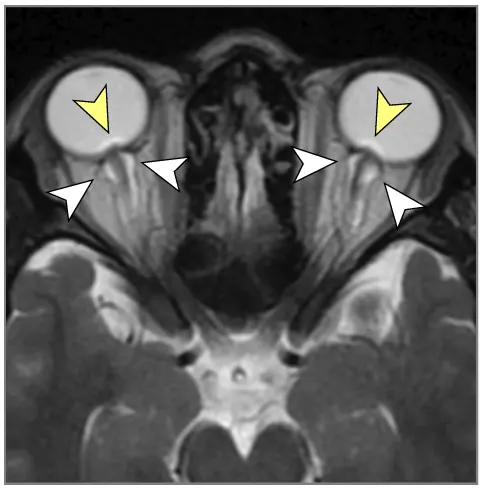

მრტ მიგნებები, რომლებიც მიუთითებს ინტრაკრანიალურ ჰიპერტენზიაზე (ხშირად ჩანს IIH-ში, მაგრამ შეიძლება მოხდეს ქრონიკული აწეული ICP-ის სხვა მიზეზებით) [9]:

- თავის ტვინის მრტ: სასურველი მოდალობა დეტალური ანატომიური შეფასებისთვის. შეუძლია აჩვენოს პარკუჭების გადიდება (ჰიდროცეფალია), გამოავლინოს ობსტრუქციული დაზიანებები (სიმსივნეები, კისტები, წყალსადენის სტენოზი), აჩვენოს მომატებული ICP-ის გართულებები (თიაქარი), აღმოაჩინოს კომუნიკაციური ჰიდროცეფალიის მიზეზები (მაგ., წინა სისხლჩაქცევის/ინფექციის ნიშნები), გამოავლინოს IIH-ის მიმანიშნებელი ნიშნები (ცარიელი კეხი, მხედველობის ნერვის გარსის გაფართოება, უკანა თვალის კაკლის გაბრტყელება, ვენური სინუსის სტენოზი MRV-ზე), ან აჩვენოს ცერებრალური შეშუპების გამომწვევი ძირითადი პათოლოგია (ინსულტი, სიმსივნე, ანთება) (7). სპეციფიკურ მიმდევრობებს (მაგ., CISS/FIESTA) შეუძლიათ შეაფასონ ლიკვორის ნაკადის დინამიკა.

| იდიოპათიური ინტრაკრანიალური ჰიპერტენზია (IIH) | თავის ტკივილი (ხშირად ყოველდღიური, პულსირებადი), პაპილედემა (ჩვეულებრივ ორმხრივი), ვიზუალური დარღვევები (გარდამავალი დაბნელება, ველის დაკარგვა), პულსირებადი ტინიტუსი, +/- CN VI პარეზი. ცნობიერების ნორმალური დონე. ტიპიურად ახალგაზრდა, ჭარბწონიანი ქალები. ნევროლოგიური გამოკვლევა სხვა მხრივ ნორმალურია (გარდა პაპილედემის/CN VI პარეზისა). | ნორმალური მრტ/კტ ტვინის სტრუქტურა (არ არის მასა/ჰიდროცეფალია). მრტ/MRV შეიძლება აჩვენოს მეორადი ნიშნები (ცარიელი კეხი, მხედველობის ნერვის გარსის გაფართოება, უკანა თვალის კაკლის გაბრტყელება, ვენური სინუსის სტენოზი). LP ადასტურებს მომატებულ გახსნის წნევას (>25 სმ წყ.სვ) ნორმალური ლიკვორის შემადგენლობით. |